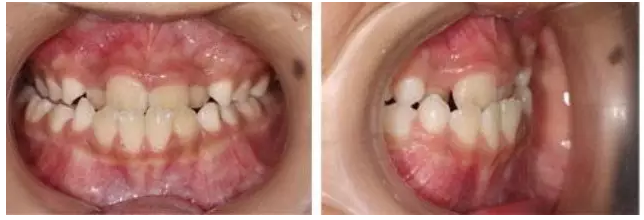

正常前牙咬合關(guān)系,是上前牙覆蓋在下前牙的前面。如果出現(xiàn)相反的現(xiàn)象,即下前牙位于上前牙的前面,就是人們常說的“地包天”,醫(yī)學(xué)上稱之為前牙反頜。“地包天”,是口腔錯(cuò)頜畸形的一種疾病,是我國兒童常見的一種錯(cuò)頜畸形,對口腔功能、顏面美觀和心理健康有較嚴(yán)重的影響,并且隨著患者的生長增齡癥狀逐漸加重。

“地包天”會造成患者口腔功能異常,包括咀嚼效率下降,咬合創(chuàng)傷等等。而且,嚴(yán)重的患者常導(dǎo)致面部凹陷,下巴明顯突出,表現(xiàn)為“月牙臉”,對患者美觀影響較大,繼而可導(dǎo)致相應(yīng)的心理問題,影響患者的正常工作學(xué)習(xí)生活。